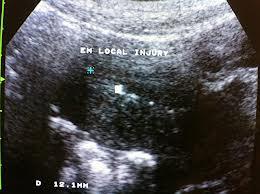

女擁雙宮懷異卵雙胎 細心安胎, 彰化博元婦產科醫院院長蔡鋒博表示,年輕的女子,因月經過期未來,經超音波檢查後赫然發現,這位女子不僅擁有醫學上相當少見的「雙角子宮」 彰化一名年輕女子,因月經未來,前往婦產科檢查後赫然發現,這位女子不僅擁有醫...